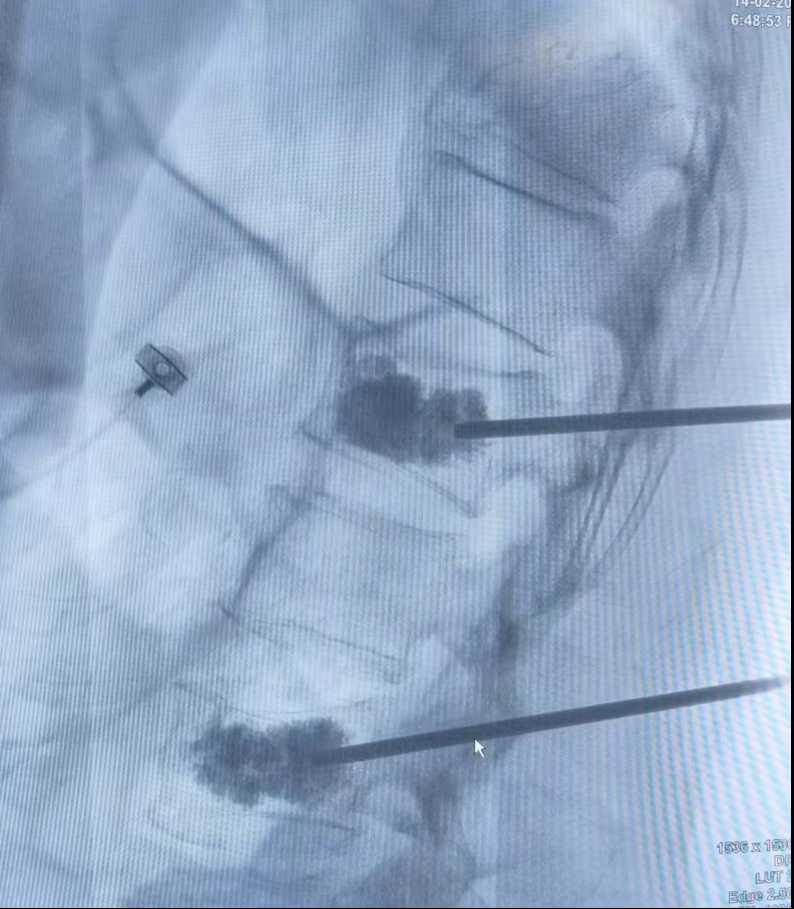

圖 2術(shù)中透視